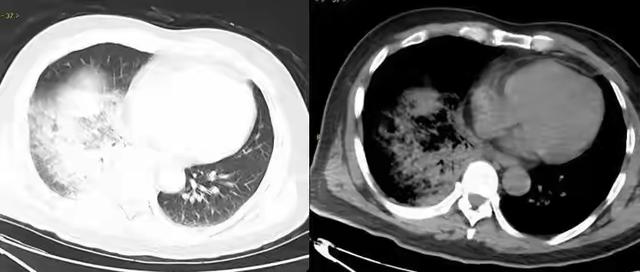

一只被藏在口袋里的宠物鹦鹉,竟让一位经验丰富的司机险些丧命。这并非耸人听闻的都市传说,而是一个真实发生的健康警示。故事的主角林师傅,将爱鸟随身携带,以为是温馨陪伴,殊不知,他正将自己暴露在一个潜伏长达45天的致命威胁之下。

这威胁,便是俗称“鸟疫”的鹦鹉热。它的元凶——鹦鹉热衣原体,并非鹦鹉的专利,而是一个潜伏在190多种鸟类和禽类身上的“隐形杀手”。从我们常见的鸽子、鸡鸭,到各类野生飞禽,都可能是它的宿主。它的传播方式也远比想象中隐蔽,并非只有被鸟啄伤才会感染。当你清理鸟笼,扬起的粉尘中可能就夹杂着病原体;当你触摸被污染的羽毛或饲料,也可能在不经意间中招。这正是“病从口入,祸从手出”的现代版写照。